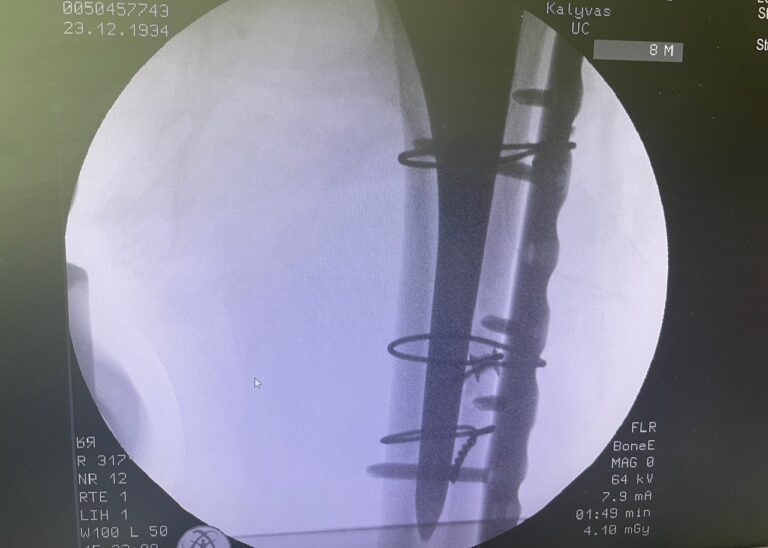

- Διαφυσιακά κατάγματα μηριαίου ή κνήμης

Διάγνωση

- Ακτινογραφία

- Χειρουργική αποκατάσταση (πλάκες, βίδες, ενδομυελικοί ήλοι)